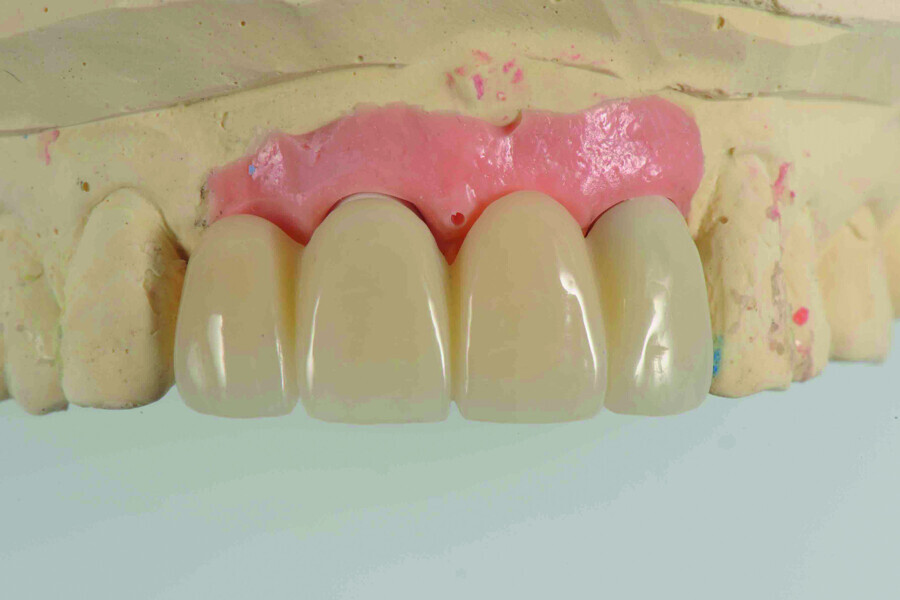

Fig. 14: Provisional restoration on the model.